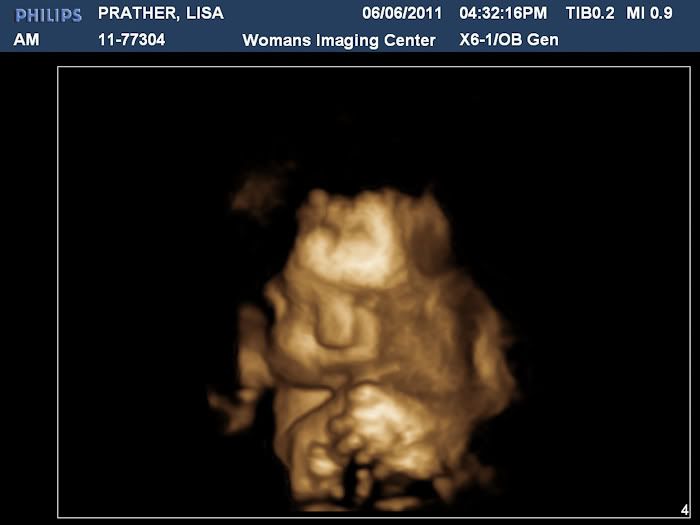

Then we got to see some in 3D, which were amazing!

Stephen thinks he has my nose and I think he has my cubby cheeks! We both think he is just adorable and can't wait to meet him!